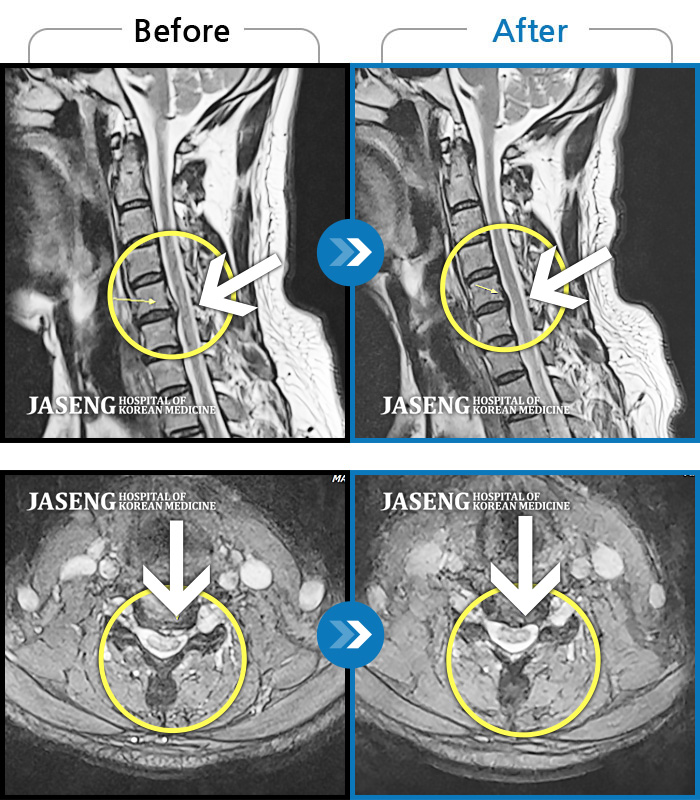

MRI 치료사례

목 양쪽 통증, 후두통에 두통